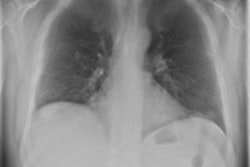

While multiparametric MRI can provide valuable morphological and functional information for diagnosing prostate cancer, these studies can be challenging for radiologists to interpret due to the various pulse sequences involved. Computer-aided detection (CAD) software can help, however, according to an Italian research team.

In a study presented at ECR 2014, Dr. Daniele Regge of the Institute for Cancer Research and Treatment in Candiolo shared the institution's experience with a CAD algorithm they developed that yields a color-coded map with per-pixel estimates of cancer probability. Click here to learn how well the system performed.